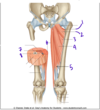

Which structure is labeled by #12?

Function?

Innervation?

Vastus lateralis

Knee extension (inserts on greater trochanter of femur)

Femoral nerve

What view of the femur is this?

Posterior view

(You can see the intercondylar notch in between the medial and lateral condyles)

Which structure is labeled by #9?

Semimembranosus